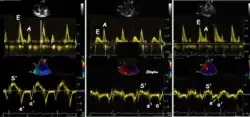

Spectral tissue velocity curves from the mitral annulus at the septal (left) and lateral (right) points. The curves show multiple heartbeats.

Pulsed wave spectral tissue Doppler has become a universal tool that is part of the general echocardiographic examination. Like any other echocardiographic measurement, measures by tissue Doppler should be interpreted in the context of the whole examination. The velocity curves are in general taken from the base of the mitral annulus at the insertion of the mitral leaflets, in the septal and lateral points of the four chamber view, and eventually the anterior and inferior points of the two-chamber views. For the right ventricle it is customary to use the lateral point of the tricuspid annulus only. Averaging peak velocities from the septal and lateral point has become common, although it has been shown that averaging all four points mentioned above, gives significantly less variability[3]

Single spectral tissue velocity curve from the mitral annulus. The curve shows velocities towards the probe (positive velocity) in systole, and away from the probe (negative velocities) in diastole. The most useful measures are the peak velocities, in systole S' and in early diastole (e') and late diastole during atrial contraction (a').

Annular velocities summarize the longitudinal contraction of the ventricle during systole, and elongation during diastole. Peak velocities are commonly used.

relation between mitral flow and mitral annulus velocity. Left: Normal person with good diastolic function; high E and e', normal E/e'. Middle, patient with diastolic dysfunction without increased filling pressure; low E and e', normal E/e' ratio. Left, patient with diastolic dysfunction and increased filling pressure; high E, low e' and high E/e'. The S' is reduced in proportion to the e'